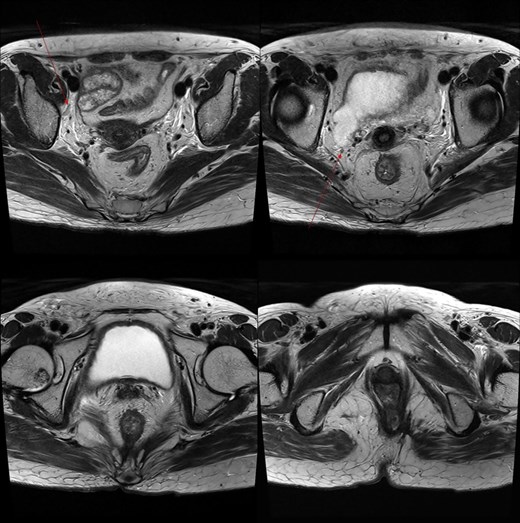

A 59-year-old female patient was referred to our hospital with severe left buttock pain lasting 5 days. Although she had no co-morbidities, she was previously diagnosed with hemorrhoids at the local clinic due to perianal pain persisting for 1 month. The patient had no medical or surgical history. Her initial body temperature was 38.4°C, blood pressure was 110/60 mmHg, heart rate was 98 beats/min, and her oxygen saturation was 98% on room air. On physical examination, erythema and hardness were noted in the left perineum and buttock areas. Additionally, dilated piles were observed on anus (Fig. 1). Given the clinical suspicion of FG, a computed tomography (CT) scan and blood tests were urgently performed. The CT scan demonstrated abscess formation along with severe emphysema in the left perineum and buttock (Fig. 2A). Blood tests showed leukocytosis of 41 840/μl with neutrophil left shift and an elevated C-reactive protein level of 33.4 ng/dl. The patient was finally diagnosed with FG, indicated by a severity index score of 6 points [6]. After initiating fluid resuscitation and broad-spectrum antibiotics, extensive debridement of the perineum was executed (Fig. 2B). However, due to clinical deterioration after general anesthesia, staged debridement was performed, and the patient was admitted to the intensive care unit for stabilization. Subsequent debridement and a diverting colostomy were performed 3 days after surgery. After 1 week in intensive care, the patient was transferred to the general ward where additional wound debridement and revisions were conducted. Two months after initial surgery, the surgical wound had completely healed, and wound closure was performed. Although inflammation had subsided, indurated tissue persisted around the anus, which had become so constricted that a digital rectal examination was impeded. Therefore, a biopsy of the perianal tissue was taken. Histopathological examination identified moderately differentiated squamous cell carcinoma, and HPV 16 was detected (Fig. 3). Pelvic magnetic resonance imaging (MRI) revealed anorectal cancer with invasion into both levator muscles and indeterminate lymph nodes in the bilateral external iliac, right obturator, and bilateral inguinal chains (Fig. 4). Positron emission tomography demonstrated an intensely hypermetabolic mass extending from the anus to the rectum, accompanied by multiple hypermetabolic lymph nodes in the left common iliac, left external iliac, right internal iliac, and bilateral inguinal regions (Fig. 5). Consequently, concurrent chemoradiotherapy (CCRT) employing mitomycin and 5-fluorouracil was initiated. The patient received a total radiation dose of 63 Gy in 35 fractions over 8 weeks. Elective nodal irradiation included the bilateral inguinal, internal iliac, and mesorectal nodal basins, in accordance with standard guidelines. Although follow-up MRI after CCRT showed a significant reduction in the size of the primary tumor and lymph nodes, we decided to perform a radical resection (Fig. 6). Robotic abdominoperineal resection was performed 3 months after CCRT, during which lateral pelvic lymph node dissection wasn’t conducted, as post CCRT imaging showed indeterminate lymph nodes suggestive of remission. Histopathological examination of the specimen revealed no residual tumor (ypT0N0). Although a minor surgical site infection occurred at the perineal wound, it was successfully treated with oral antibiotics and dressings at an outpatient setting. At 10 months post-surgery, the patient reported left pelvic pain, and follow-up imaging revealed suspected metastases in the left psoas, para-aortic area, supraclavicular node, right 10th rib, and lung. Consequently, the patient was scheduled for palliative chemotherapy.

Pelvic MRI demonstrating the progression and extent of perineum and pelvic involvement. (A–C) Indeterminate lymph nodes in the bilateral external iliac chains, right obturator chain, and bilateral inguinal chains (thin arrow). (D) Presence of anorectal cancer with invasion of both levator muscles (thick arrow).